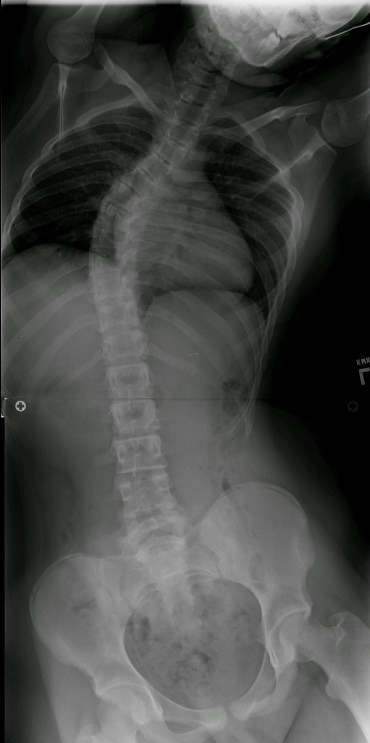

Posterior Spinal Fusion and Rod Placement – Before rod insertion